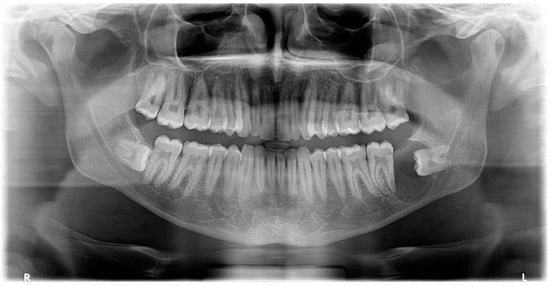

The oral clinical examination was unremarkable, and the patient was asymptomatic. On the OPG, a pericoronary radio-transparent lesion around impacted tooth #38 was discovered (Figure 8). The involved tooth was oriented mesially. The lesion was poorly delimited, measured 24 × 10 mm, and stretched to the apparently resorbed distal root apex of tooth #37. The roots of tooth #38 clearly overlapped with the IAC, raising suspicion of interference. The OPG images were indicative of a DC with possible secondary infection and perilesional sclerosing osteitis.

On an OPG X-ray, teeth #38 and 48 were impacted and distally orientated (Figure 10). Tooth #38 showed a radiotransparent lesion measuring 20 × 15 mm, with a well-defined border, multilocular appearance, and a thin septum, most compatible with a DC versus ameloblastoma versus odontogenic keratocyst.